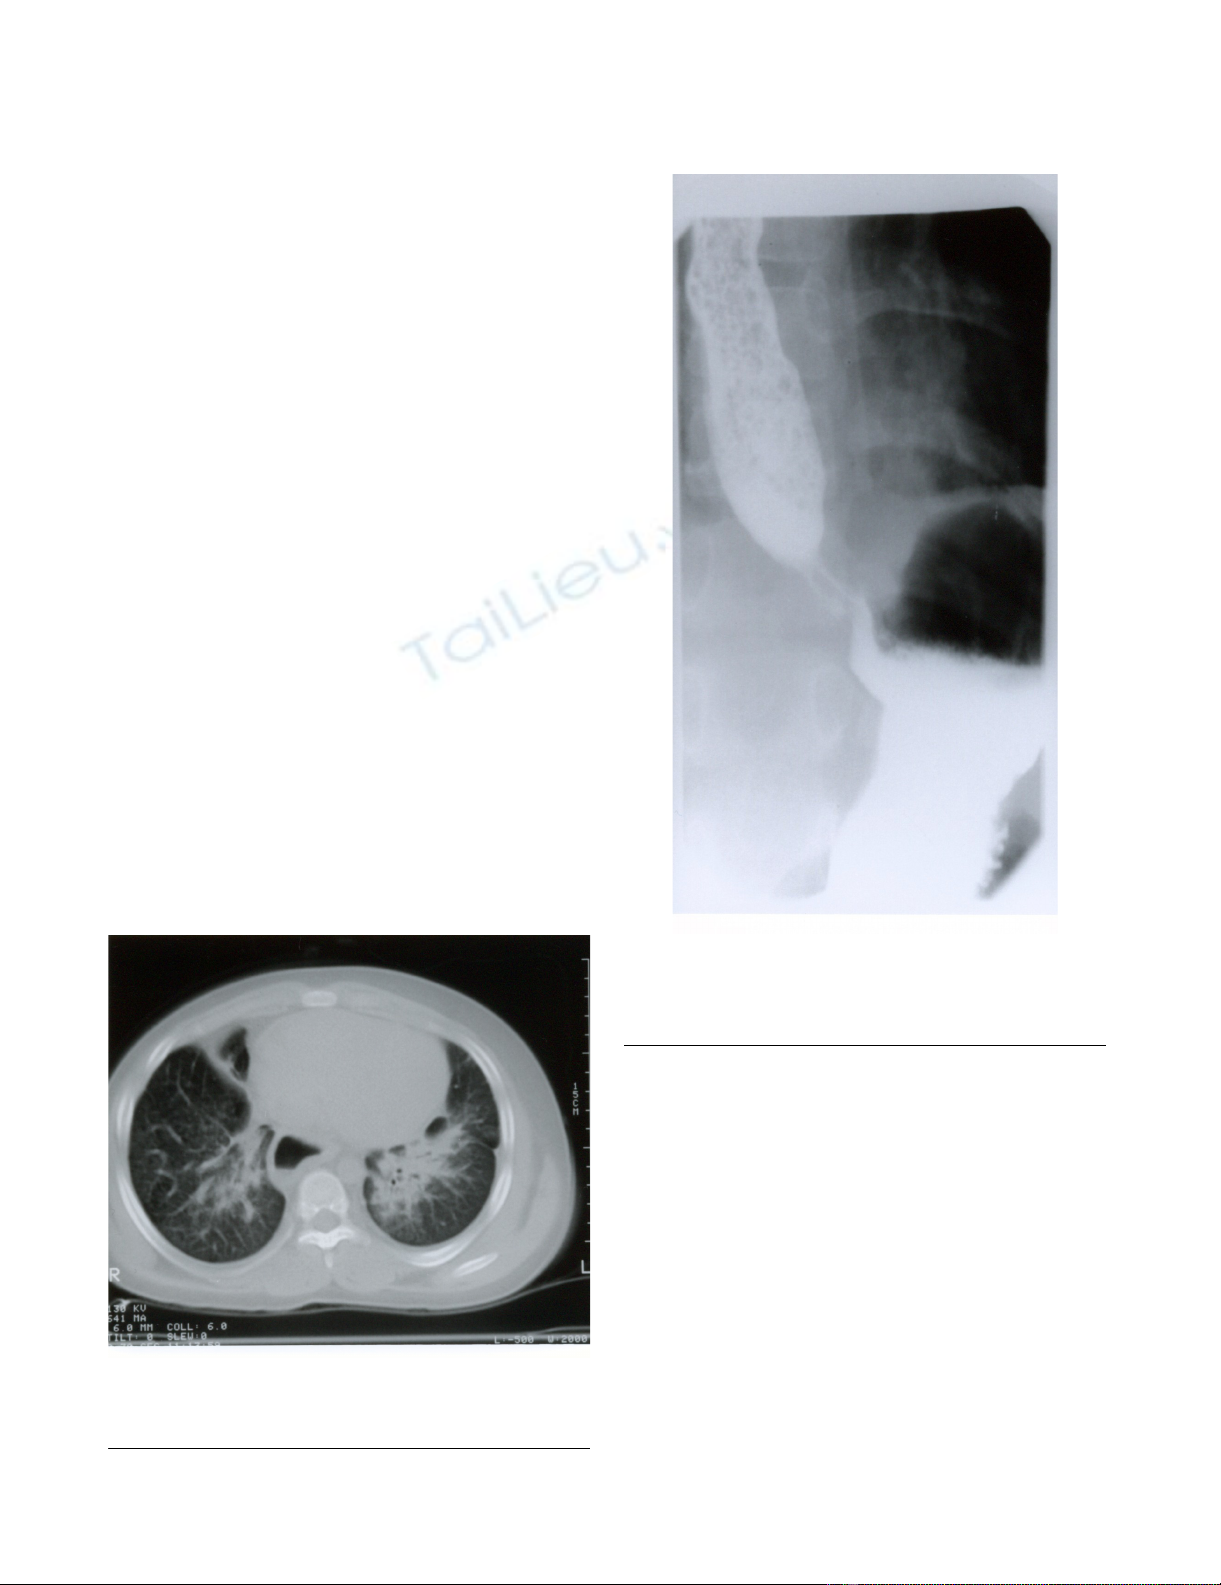

CT scan of the chest showed diffuse lung infiltrates that

seemed worse on right middle lobe and left lower lobe.

The esophagus was enlarged along its entire length but

with no obvious tracheal compression (figure 3). In view

CT scan of chest showing bilateral lung opacification with septal thickening and esophageal dilatationFigure 3

CT scan of chest showing bilateral lung opacification

with septal thickening and esophageal dilatation.